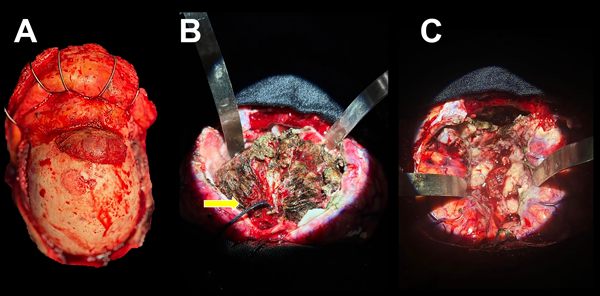

A nivel intradural e interhemisférico se comprobó lesión extraaxial de gran volumen con desplazamiento de ambos lóbulos frontales hacia lateral y posterior. Se efectuó desvascularización de la superficie tumoral con coagulación bipolar y debulking central con aspirador ultrasónico y disección microquirúrgica subpial de manera circunferencial hasta el límite anteroinferior representado por las arterias pericallosas, las que se disecaron y protegieron. Se realizó resección completa con coagulación de aparente base de implantación, hemostasia de lodge quirúrgica, duroplastia con periostio, cranealización de senos frontales y craneoplastia bifrontal con cemento óseo (Figuras 3 y 4).

Figura 4. Hallazgos intraquirúrgicos. A) Lesión exofítica transcraneana bifrontal. B) Superficie tumoral tras coagulación bipolar. Se observa ligadura de seno sagital superior en su porción anterior (flecha amarilla). C) Lodge quirúrgica libre de lesión.